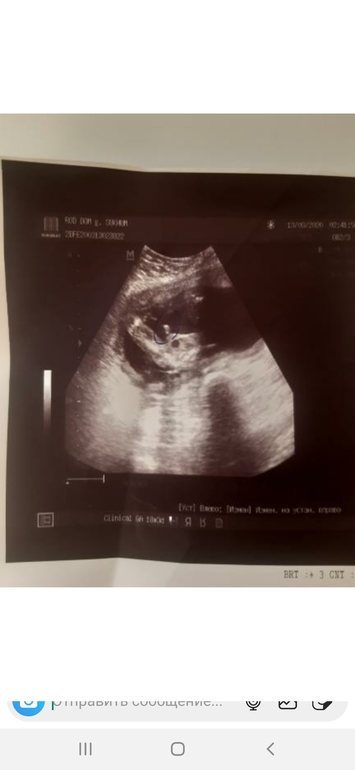

Александра, здравствуйте, а тут что скажите?

У дочки похоже очень было как на Вашей фотке.))) А у нас, да, мальчик родился. В 13 недель отчётливо торчал перчик))

Мальчик у Вас , у моих двух так торчало , а у дочки прям лежал этот половой бугорок )